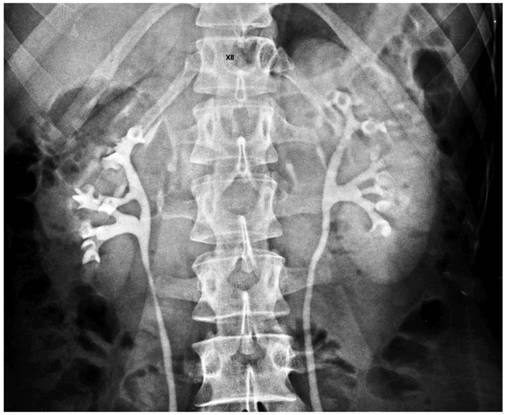

Bolnavul este condus la serviciul de urografie. Este ajutat sǎ se dezbrace si sǎ se aseze in decubit dorsal pe masa radiologicǎ.

Se face testarea sensibilitǎtii organismului la substanta de contrast.

Se injecteazǎ un ml Odiston intra-venos prin omogenizare cu sangele. Se comunicǎ pacientului sǎ nu se sperie la unele simptome ce pot sǎ aparǎ: ameteli, greturi sau dureri abdominale care dispar repede si fǎrǎ consecinte. Pentru prevenirea lor, substanta de contrast se poate administra si sub forma de perfuzie intravenoasa in solutie de glucoza 5% administrand o cantitate totala de 250 ml lichid in 15 min. Prin aceasta metoda se poate asigura opacifierea mai intensa si de o durata mai lunga

Dacǎ pacientul prezintǎ reactii hiperalergice se intrerupe administrarea si se vor aplica masurile terapeutice de urgenta.

Dacǎ toleranta este bunǎ se administreazǎ intra-venos substante de contrast:

-pentru adulti: -20 ml Odiston 75%

-25 ml Odiston 60%

-pentru copii - in functie de varstǎ

-5-15 ml Odiston 60% sau 50%

La 8-10 minute de la efectuarea injectiei se executǎ radiografii in serie, aproximativ la 30; 60; 90; 180 minute.

Dupǎ examen pacientul este condus la salon.

Examenul se noteazǎ in foaia de observatie.

Urografie